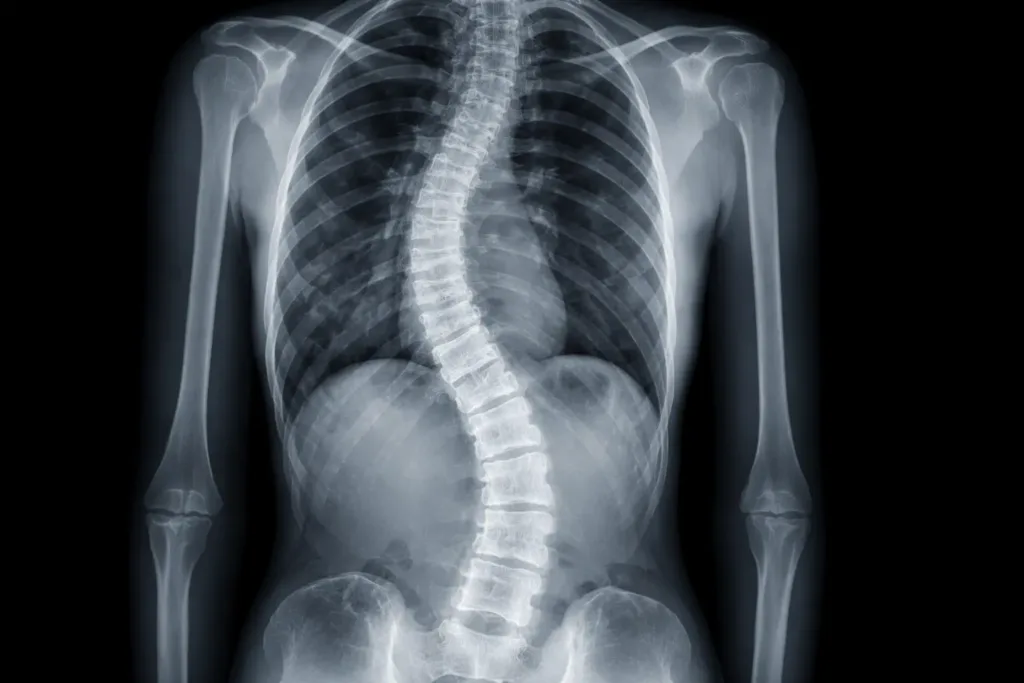

“Scoliosis”

Scoliosis is a sideways curve. A report may describe the direction (left or right), location, and sometimes angle. Some curves are structural; others are “functional” and appear during pain episodes or protective muscle tightening.